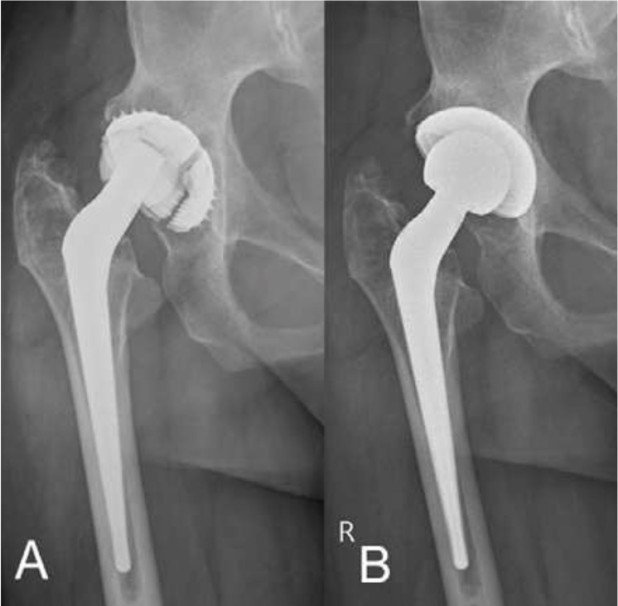

Fall 2

44-jähriger Patient, seit 21 Jahren mit Hüftprothese und vollkommen aufgebrauchtem Kunststoff (Polyethylen)-Inlay. Der Keramikkopf hat direkten Kontakt mit dem Metall der Gelenkpfanne, was zu vermehrtem Metallabrieb am Implantat führt (Abb.5). Obwohl der Patient bis auf eine zunehmende Bewegungseinschränkung kaum Schmerzen hatte, wurde das Risiko des andauernden Metallabriebs besprochen und die Pfanne über einen minimalinvasiven Zugang gewechselt. Der Patient, der multiple mit Rheumatoider Arthritis assoziierte Gelenksbeteiligungen hat, konnte früh mit Vollbelastung mobilisiert werden. Krücken müssen in so einem Fall nicht zwingend zu Hilfe genommen werden, insbesondere dann, wenn es Schultern, Ellbogen und Hände nicht zulassen. Bereits nach vier Wochen kehrte der behandelte Patient an seinen Arbeitsplatz zurück.